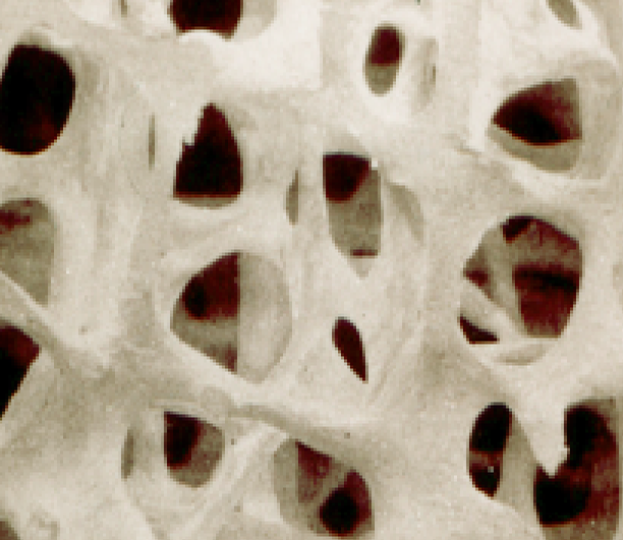

UNHEALTHY BONE

Many people think that their bones are just like timbers or steel which supports the structure of a house. They are not. Bones absolutely support us, but bones are an ever-changing, living and dynamic organ. More below.